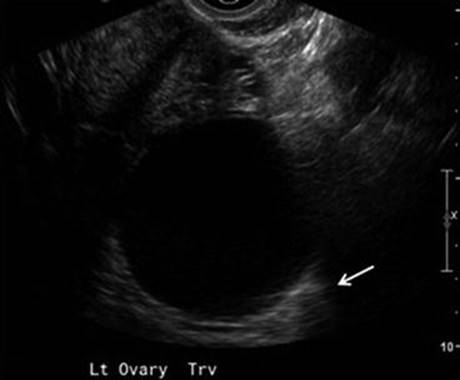

Transvaginal ultrasound is usually sufficient to characterize simple cysts , though cysts greater than 7 cm may be difficult to completely visualize, for which MRI may be useful [54]. Simple cysts are thin-walled, anechoic structures with no complex features, such as thick septations, mural nodularity, papillary excrescences, or hypervascularity (Fig. 4.2). In asymptomatic premenopausal women, simple cysts less than 5 cm are very low risk for malignancy and do not strictly require follow-up [54]. Simple cysts up to 1 cm can be seen in postmenopausal women and confer very low risk for malignancy; follow-up is not strictly necessary but is at the discretion of the clinician [54]. In premenopausal and postmenopausal women, larger simple cysts, measuring up to 10 cm, are generally followed with serial ultrasounds; a repeat ultrasound within 3 months is prudent, as two-thirds will resolve over time [2]. Stable cysts less than 10 cm can be followed with an annual repeat ultrasound, unless patients become symptomatic or sonographic features concerning for malignancy develop [54].

Fig. 4.2

Simple/follicular ovarian cyst. Transvaginal ultrasound demonstrates an anechoic 6-cm cyst with a thin wall and posterior acoustic enhancement (arrow) (Reprinted from Amirbekian and Hooley [51], with permission from Elsevier)